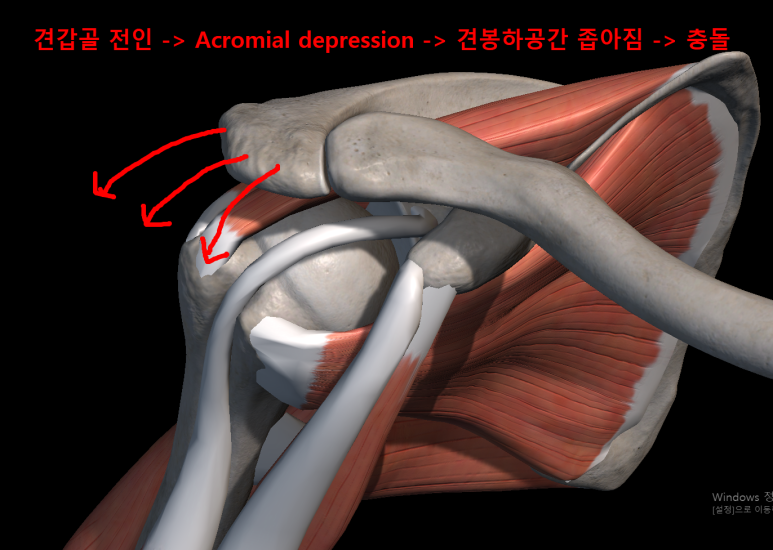

후만과 거북목으로 인해 견갑골이 앞으로 빠지는 전인상태(Scapular protraction)이 되면서 견봉하공간이 좁아지면서 어깨 충돌가능성이 증가할 수 있습니다.

앞서 말했던 원인들에 의해서 겹갑골은 과도한 견갑골의 앞으로 빠진상태인 전인상태(견갑골 벌어짐, Protraction, 후인이 잘 안됨)와 견봉 올림(Acromial elevation)이 어려움에 의해서 충돌이 더욱 쉽게 일아날 수 있습니다.

굽은등, 거북목 -> 견갑골 전인상태 -> 견봉하공간 좁아짐 -> 충돌 증가

소흉근, 이두근 단두의 단축 -> 앞쪽기울임(Anterior tilting) 상태가 유지 -> 충돌 증가

과도한 어깨 앞으로 빠짐상태인 전인 상태가 유지되고, 후인은 잘 되지않게되면 견관절의 관절와(Glenoid)에 해부학적문제가 아닌 기능적인 앞쪽기울어짐(fuctional anteversion)이 발생되면서 관절와순(Glenoid labrum)에 상완골두가 잘 밀착되지 않고 붕 뜨게 되면서 앞쪽 어깨의 안정성이 떨어지면서 손상에 취약하게 됩니다. 이는 결국 어깨 전방 탈구(Anterior dislocation, 어깨 탈구의 95% 차지, https://www.youtube.com/watch?v=xDePRKeB4kc)가 더 쉽게 발생할 수 있게됩니다.

반면 어깨 뒤쪽은 상대적으로 관절와와 상완골두가 좁아지며 외회전, 수평외전 시 극상근, 극하근이 관절와순과 충돌이 많아지며 내적충돌을 일으킬 수 있습니다.(Internal impingement) 이 때 내적충돌은 전상방, 후상방에서 각각 일어날 수 있고, 주로 후상방에서 나타납니다.